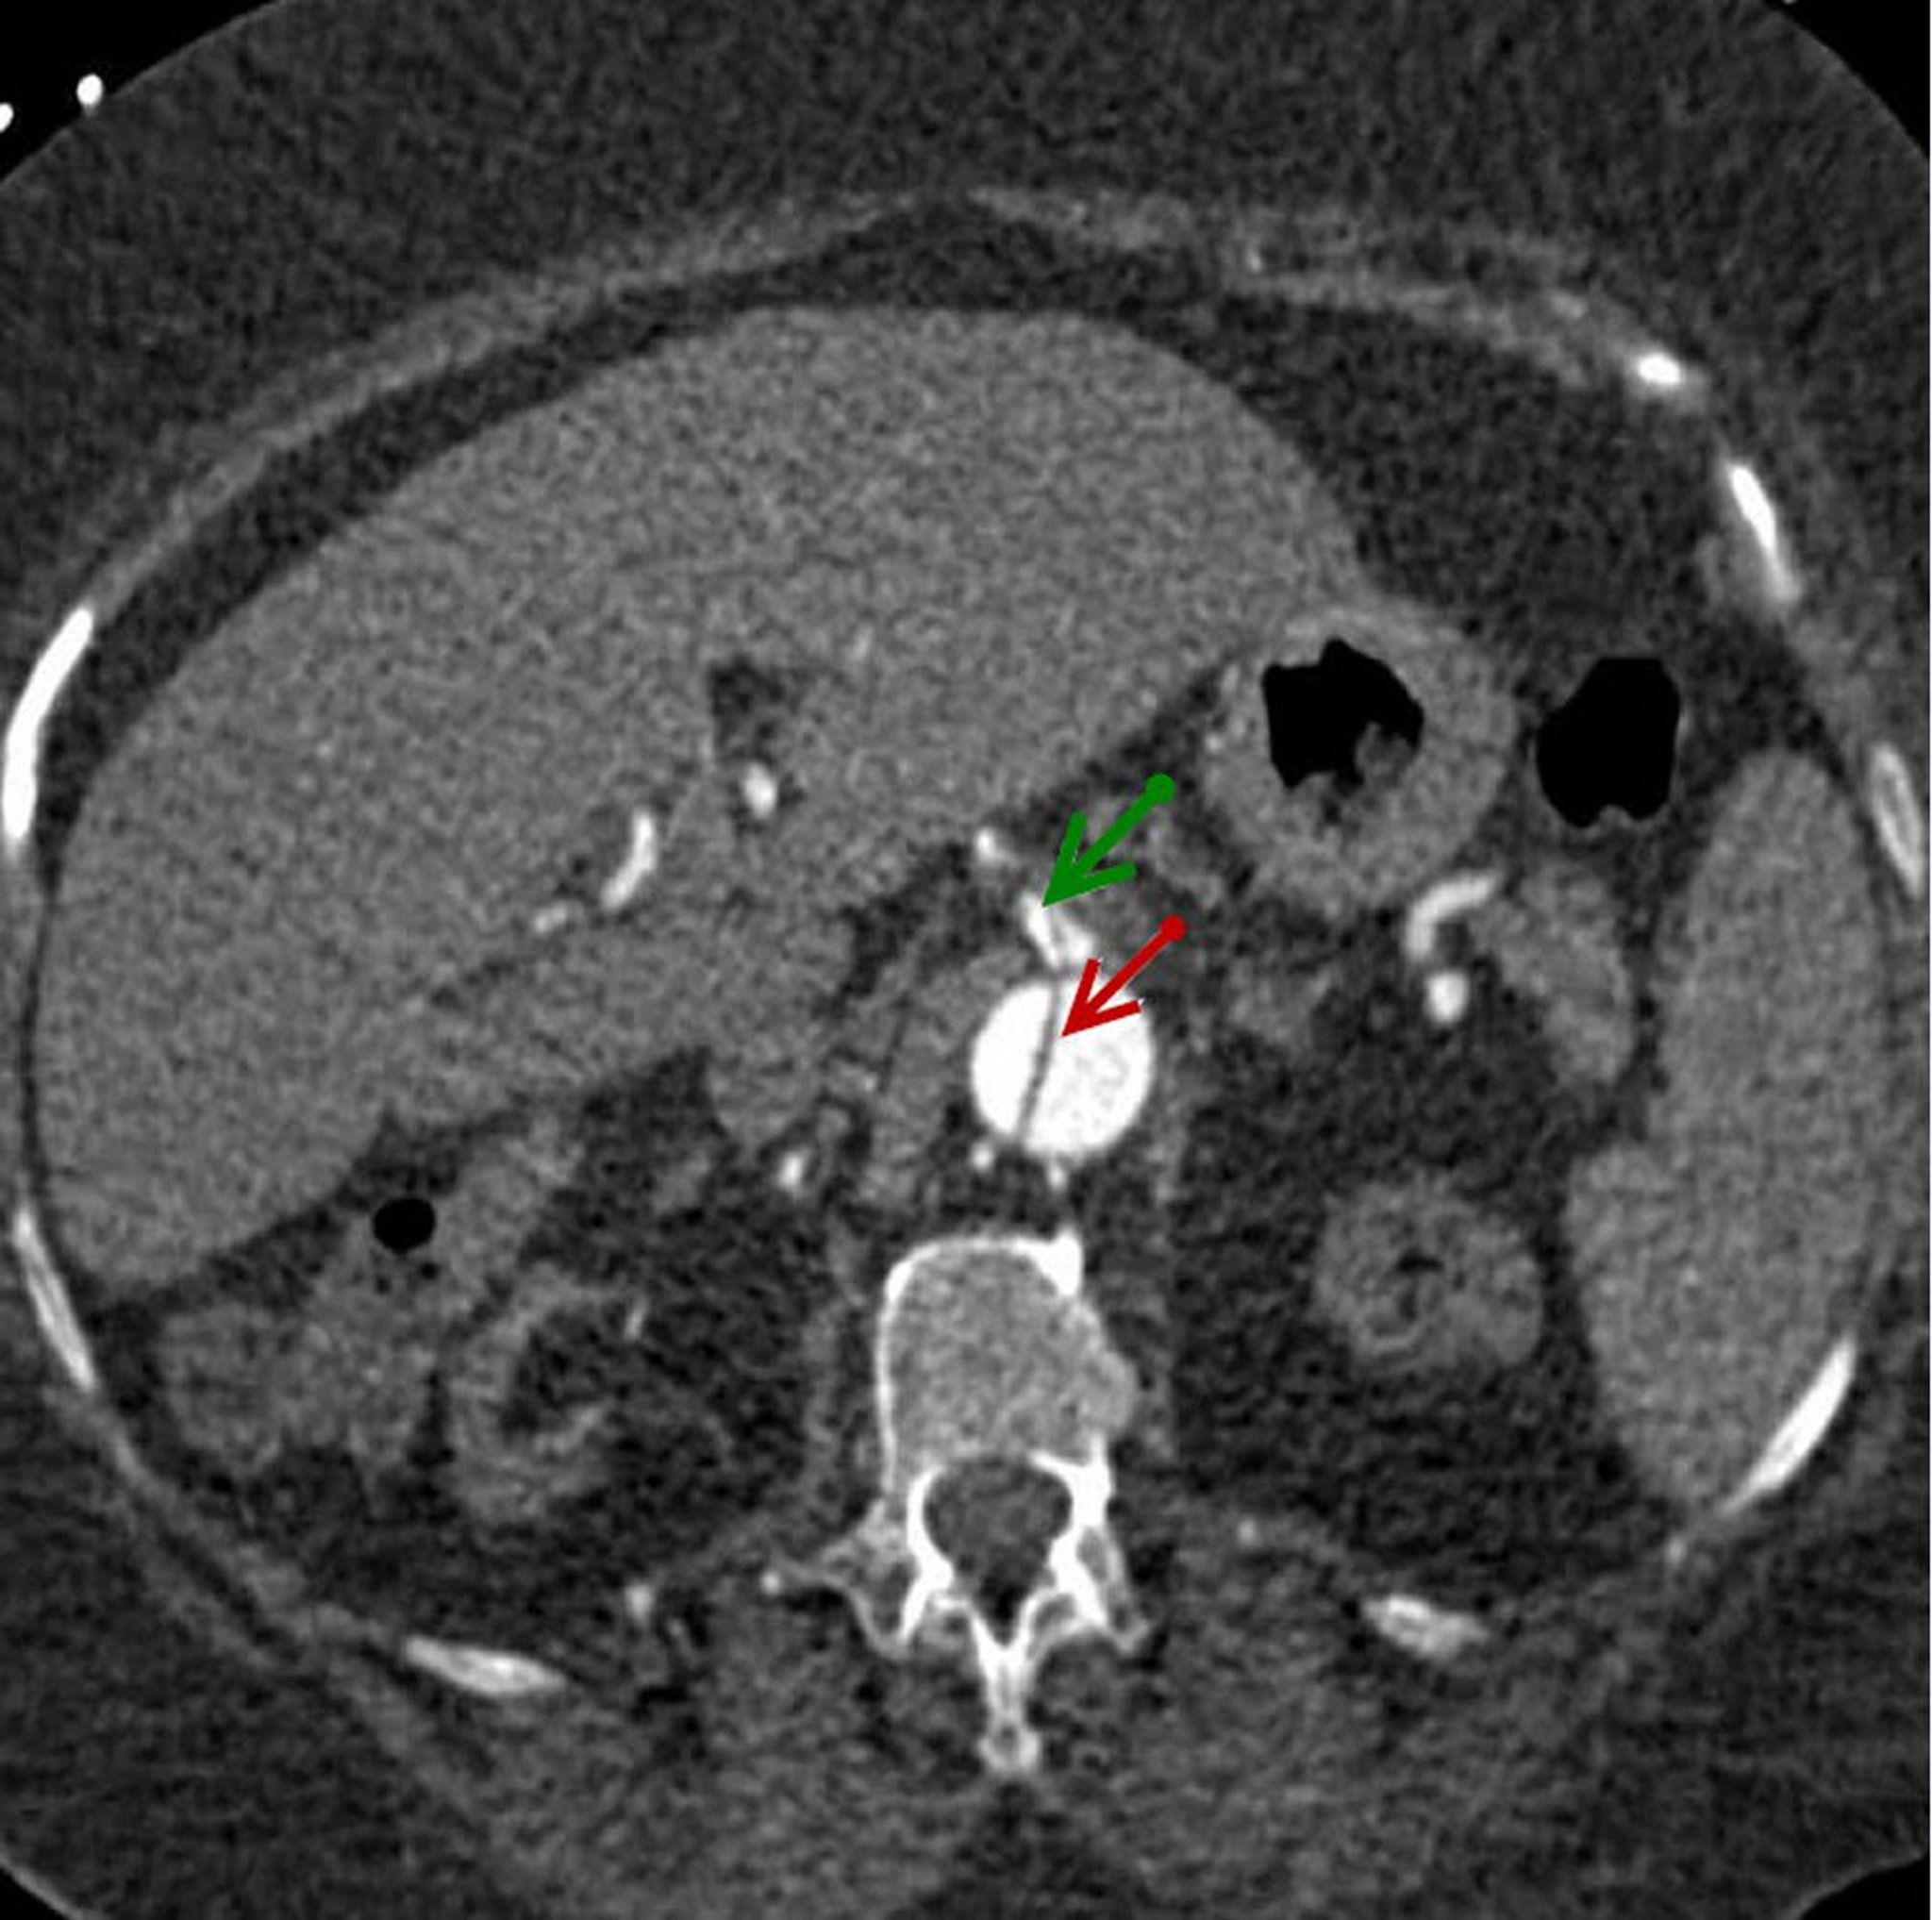

Axial image of dissection flap in descending abdominal aorta (red arrow) that extends into superior mesenteric artery (green arrow).